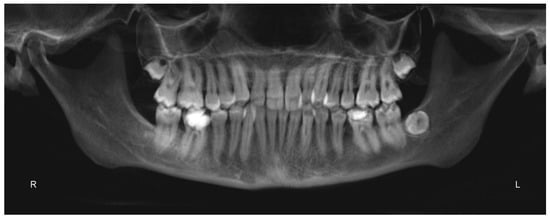

A 25 years old female attended consultation for orthodontic treatment to enhance the aesthetic of the smile. In particular, the chief complain was the crowded teeth along with the presence of wide buccal corridors while smiling. Facial analysis revealed retrognatic profile with labial competence, no gingival exposure during smiling along with extensive buccal corridors (Figure 7a–c). Intra-oral examination revealed class I molar and canine relationships, significant maxillary and mandibular crowding, mild maxillary transversal deficiency with cross-bite on the right side due to mandibular shift toward cross-bite side, significant anterior overbite (Figure 8a–e). Panoramic examination showed healthy condition of the upper first molars that would support the dental anchorage of the MSE device (Figure 9). Cephalometric analysis (Figure 10a,b) confirmed that the patient presented skeletal class I maxillo-mandibular relationship with retruded profile, mesiofacial growth pattern and anterior overbite. Patient approved the usage of photographic and radiographic records for the purpose of publication, by signing a specific form.

Figure 9.

Panorex.